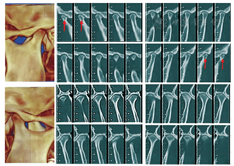

全口曲面断层片检查:18、28、38、48存在;余牙牙根基本平行;双侧下颌升支较短(43 mm)。关节CT检查:左右髁突前斜面磨平,骨皮质毛糙;双侧关节窝骨质未见明显异常,双侧髁突位置大致位于关节窝中央(图2)。X线头影测量显示:上颌骨位置大致正常,下颌骨性后缩,上前牙代偿性直立,下前牙代偿性唇倾,高角面型。

重新评价:关节CT检查显示双侧关节骨质无明显变化,左侧髁突前间隙略减小。前牙覆盖增大,水平开

,左侧磨牙关系由中性变为远中尖对尖关系(图3图4)。右侧磨牙关系仍为完全远中关系。